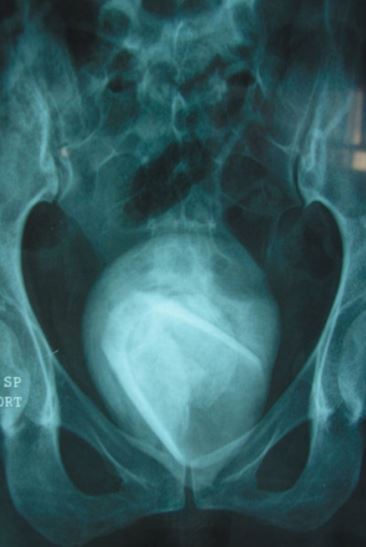

A 45-year-old woman who visited the hospital, thinking she had a minor urinary tract infection (UTI), was left in shock after doctors discovered that she had a tumbler stuck in her bladder.

At the hospital, a scan revealed that she had an 8cm-wide bladder stone inside her.

But it was the contents of the stone that baffled doctors at the Habib Bourguiba University Hospital in the eastern city of Sfax.

Inside the bladder stone, doctors found a small drinking glass, which had apparently been put up there a few years ago for "s3xual pleasure".

Her urine had shown a red blood cell range of 23-25, when the normal human will only show four or less, a report states.

The object was removed via open surgery, and she was discharged two days later. She is now thought to be fully recovered